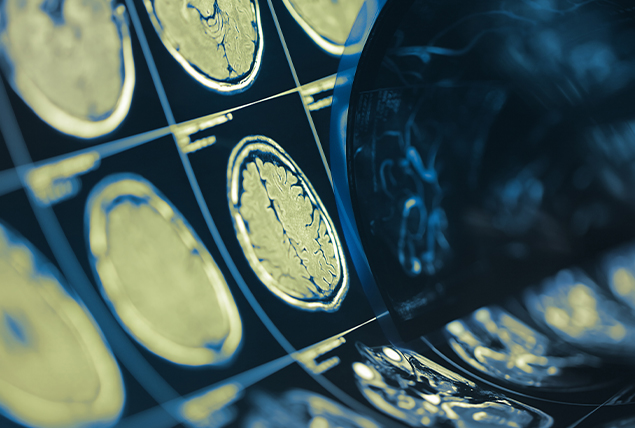

The two organs control key underlying factors that support the entire process of erections.